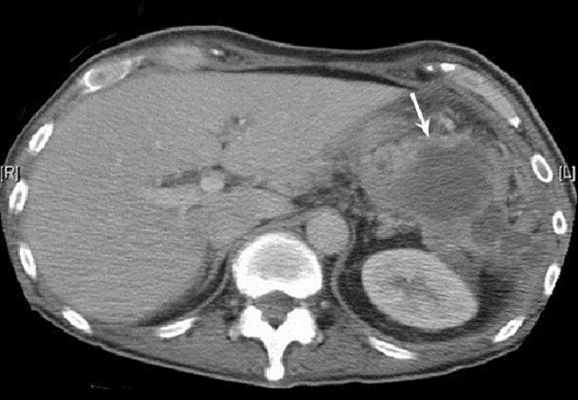

Помимо клинической картины и характерных для воспаления изменений в лабораторных показателях, диагностическую ценность имеют визуализационные исследования. Наиболее информативным методом является компьютерная томография области диафрагмы, поскольку этот метод позволяет четко выяснить анатомические особенности расположения абсцесса и выбрать правильный доступ. Ультразвуковое исследование позволяет выявить жидкостное содержимое в полости абсцесса. При рентгенологическом исследовании отмечают ограничение подвижности диафрагмы с соответствующей стороны, выпот в соответствующем плевральном синусе.

Методы исследования • Анализ периферической крови — нейтрофильный лейкоцитоз, сдвиг лейкоцитарной формулы влево, увеличение СОЭ • Посев крови на стерильность • Рентгенологическое исследование органов грудной и брюшной полостей •• Высокое стояние и ограничение подвижности купола диафрагмы •• Наличие уровня жидкости под диафрагмой, смещение соседних органов •• В лёгких — ателектазы, пневмонические фокусы в нижних сегментах •• Выпот в плевральной полости на стороне поражения • КТ, УЗИ, радиоизотопное сканирование с использованием 67 Ga.